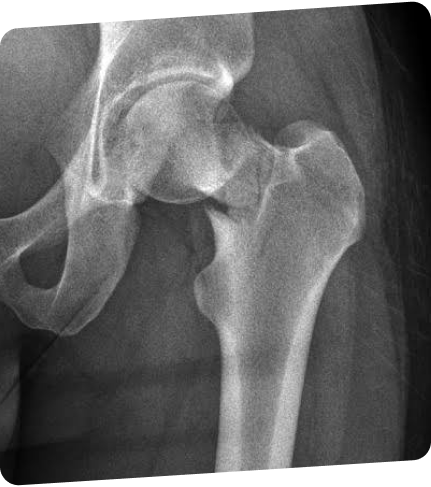

In women > 50 years of age,

83% remain undiagnosed and 88% remain untreated one year after experiencing a fracture1,*